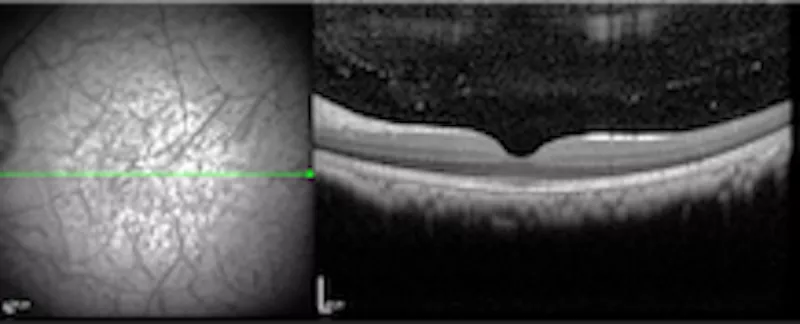

The team's work therefore focuses on the fine control of surgical parameters in order to guarantee stable and comparable experimental conditions. These include the optimization of targeted subretinal and intravitreal injections, the development of robust experimental models of macular degeneration, as well as the exploration of new surgical approaches for the management of macular edema resistant to conventional treatments. The whole is based on high-resolution multimodal imaging to precisely monitor the spread of treatments and to detect inflammatory or toxic phenomena early.

To overcome the limitations of manual techniques, the team is developing a robotic-assisted surgery platform that can filter micro-tremors, fine-tune injection speed, pressure, and flow, maintain consistent operating parameters from one procedure to the next, and integrate real-time 3D imaging and intraoperative OCT. At the same time, new personalized surgical instruments are being designed using 3D printing, with particular attention to morphological adaptation and the use of recyclable materials.